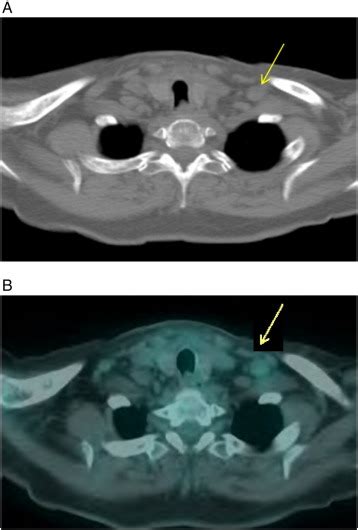

(PDF) Head & Neck Cancer with Lung Metastases: Treatment Challenges